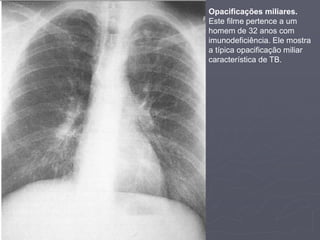

Opacificação Miliar

► Na opacificação miliar, os pulmões apresentam

aspecto mosqueado. Isso pode ser devido à

opacificação miliar ou uma aparência de “vidro-

fosco”. Você precisa, primeiro, distinguir os dois.

1. Distribuição da opacificação:

1. Observe a distribuição da opacificação na periferia. Se

a opacificação está presente na periferia então está

muito provável de ser patológico, pois, algumas vezes,

os vasos podem mimetizar um infiltrado intersticial,

mas isto só ocorre no centro dos campos pulmonares.

2. Natureza e número de opacidades:

1. Observe de perto o Rx. Na opacificação miliar, elas

devem aparecer bastante discretas

2. Se a opacificação é miliar, elas devem possuir

densidades e tamanhos similares.

3. Se a opacificação é devido a um infiltrado em vidro-

fosco, então a densidade e tamanho irão variar.

3. Base pulmonar:

1. Observe as bases pulmonares. A anatomia normal da

base pulmonar deve ser visível na opacificação miliar,

mas pode estar borrada na opacificação em vidro-

fosco.

► Se você reconhece a opacificação como miliar, então procure pistas para

sua causa. As possibilidades mais prováveis são:

▪ TB

▪ Sarcoidose

▪ Metástase miliar.

1. Observe a distribuição:

1. A opacificação miliar por TB é mais proeminente nos ápices, enquanto na

sarcoidose é mais predominante na região perihilar e terços médio do pulmão.

2. Já a metástase miliar, a predominância é nos terços inferiores dos pulmões.

2. Observe a densidade:

1. Altas densidades (muito branco) indica mais ser devido a pneumoconioses ou

TB calcificada.

2. Densidades menores pode ser metástases secundárias, sarcoidose ou outra

causa de mosqueteamento miliar.

3. Olhe o resto do Rx:

1. Procure por sinais de outras doenças.

2. Observe o hilo. Alargamento unilateral do hilo sugere TB, enquanto bilateral

sugere sarcoidose.

Opacificações miliares.

Este filme pertence a um

homem de 32 anos com

imunodeficiência. Ele mostra

a típica opacificação miliar

característica de TB.